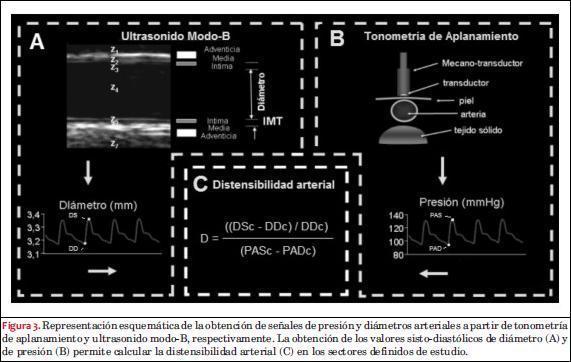

Onda del diámetro del pulso carotídeo y espesor íntima-media

Una vez obtenida la secuencia de imágenes del video se realizó el análisis mediante un equipo de procesamiento específico (Hemodyn 4M, Dinap SRL, Buenos Aires, Argentina). A partir de la aplicación del software a la secuencia de imágenes obtenida, se eligió una región de interés en un corte longitudinal de la arteria carótida común (a 1 cm del bulbo carotídeo) y se detectaron de manera automática los bordes de las paredes arteriales a partir de cambios en la impedancia acústica (Z) de los materiales, obteniendo para cada video la morfología del diámetro del pulso arterial latido a latido (con sus valores sisto-diastólicos) y el IMT de la pared posterior en el fin de la diástole (figuras 2 y 3A).

Onda de presión arterial carotídea 5ras

De manera no invasiva, y posterior a la visualización ultrasonográfica de las arterias carotídeas, se obtuvo la onda de presión de la arteria carótida común mediante la utilización de un tonómetro de aplanamiento (SphygmoCor 7.01 AtCor Medical, Sydney, Australia) (figura 3B). El transductor fue colocado a nivel superficial sobre la piel en el sector de máxima pulsación arterial carotídea y alejado de los sectores de placa de ateroma en el caso que hayan sido identificadas previamente. Se asumió que la PA a lo largo del vaso es uniforme en el segmento estudiado, ya que fueron excluidas PAC con obstrucción significativa al flujo arterial. Las señales fueron grabadas y analizadas off-line utilizando un software del equipo que permite el calibrado de la señal de presión carotídea. Brevemente, el calibrado de la señal toma en cuenta que la PA diastólica y media no se modifican en forma sustancial del centro (por ejemplo, arteria carótida) a la periferia (por ejemplo, arteria braquial) en un individuo en posición de decúbito supino, de modo que al obtener la morfología de la PA carotídea y los valores de PA diastólica y PA media braquiales es posible el calibrado de la señal carotídea adjudicándole la información braquial y ajustando linealmente los valores intermedios de la onda(33).

Análisis de la distensibilidad arterial en el eje longitudinal de PAC y carótidas control

En dichos sectores se cuantificaron los niveles de distensibilidad (distensibilidad arterial sectorial), como parámetro de rigidez arterial local, para las arterias del G1 y G2, a partir de la obtención de la PA y diámetro sectoriales previo al promediado de cuatro latidos sucesivos mediante la siguiente ecuación(34):

donde DSc y DDc constituyen el diámetro sistólico y diámetro diastólico carotídeo obtenidos en cada sector, respectivamente, mientras que PASc y PADc corresponden a los valores de PA sistólica y diastólica carotídea (figura 3C).